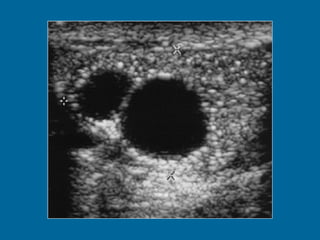

Intratesticular cyst in a 50-year-old man.  (a) US image shows a right-sided 17- mm-diameter intratesticular cyst.  (b) T2-weighted image shows that the lesion (arrow) has the characteristic high signal intensity of fluid. The surrounding thin rim of testicular parenchyma enables diagnosis of an intratesticular cyst. However, note that there is some overlap in imaging appearances of an intratesticular cyst and a tunica albuginea cyst. No further intervention was performed.

Intratesticular cyst ina 50-year-old man. (a) US image shows a right-sided 17- mm-diameter intratesticular cyst. (b) T2-weighted image shows that the lesion (arrow) has the characteristic high signal intensity of fluid. The surrounding thin rim of testicular parenchyma enables diagnosis of an intratesticular cyst. However, note that there is some overlap in imaging appearances of an intratesticular cyst and a tunica albuginea cyst. No further intervention was performed.